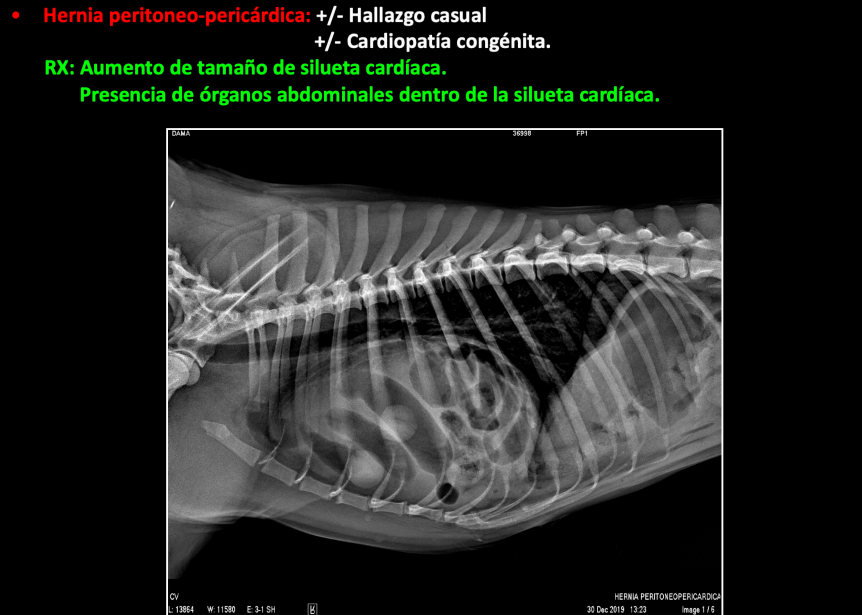

Rotura diafragmática

Adquirida. Normalmente por traumatismo.

Desplazamiento craneal de órganos abdominales.

RX:

- Aumento de opacidad en la cavidad torácica.

- Órganos abdominales dentro de la cavidad torácica.

- Pérdida de definición del diafragma.